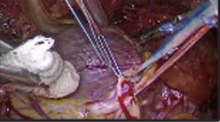

Obesity is often considered as a contraindication to minimally invasive coronary artery bypass grafting. Our concept has been that all incoming patients for isolated surgical coronary revascularization are eligible for a coronary artery bypass grafting through the left anterior minithoracotomy. For this purpose TCRAT procedure (Total Coronary Revascularization via Left Anterior Thoracotomy) was developed. The purpose of this study was to examine the outcomes of routine use of aforementioned surgical procedure in obese patients and determine if this approach is warranted.

We retrospectively reviewed 349 consecutive multivessel minimally invasive coronary grafting procedures done at our institution between July 2017 and January 2020, which represents the 98% of all patients who underwent isolated CABG in the same time frame. The outcomes of those who had obesity, defined as patients with a body mass index of greater than 30 kg/m2 were compared with non-obese patients. These groups were compared for differences in operative variables including cross clamp and cardiopulmonary bypass times as well as postoperative outcomes which included intubation times as well as ICU and hospital LOS. Postoperative complications including bleeding (return to OR) and infection (surgical wound) were also collected.

Non-obese and obese groups are not significantly different with regard to numbers of a distal anastomosis (3.05±0.66 vs 2.94±0.66) Our study results showed that patient with obesity had longer total operation time (272.9&plus mn;55.6 vs 259.6±50.4 in non-obese group) and longer CPB time (145.9±37.5 vs 134.9±30.8), Regarding postoperative characteristics, obese patients also stayed longer in ICU (2.34±1.7 days against non-obese group - 2.02±0.38 days) Total hospital mortality was 1.2% in obese group of patients.

Our results would suggest that minimally invasive coronary grafting with TCRAT technique could be routinely applied in obese patients with results that are not clinically different from non-obese patients.